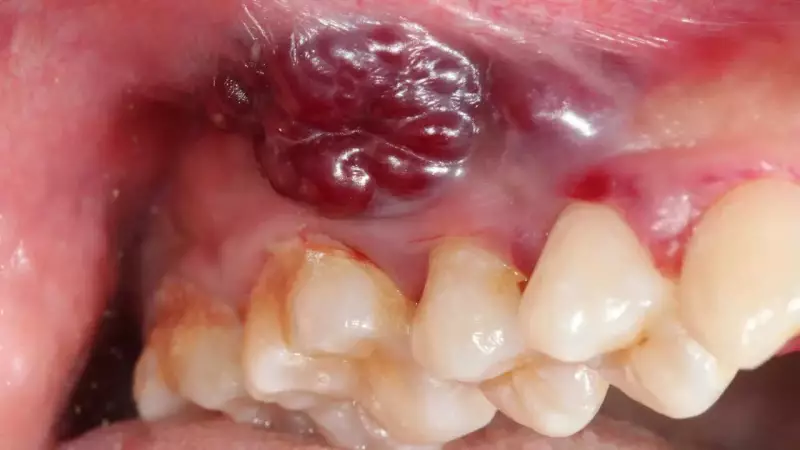

Medical research now clearly identifies a non-healing ulcer inside the mouth or on the lips as a critical early indicator of potential oral cancer. A peer-reviewed study published in the Journal of Oral Biology and Craniofacial Research found that persistent ulcers, along with white or red patches, were common early signs of oral squamous cell carcinoma. The study specifically highlighted that lesions lasting longer than two weeks without improvement should raise suspicion.

The danger lies in their deceptive nature. These chronic lesions often appear harmless and are frequently painless in the initial stages, leading many to dismiss them as minor irritations. This dismissal is a primary reason for late-stage diagnosis. The research emphasises that early medical evaluation is crucial, as paying attention to these subtle changes can genuinely save lives.

Unlike common ulcers, cancer-related sores may have raised edges, feel rough, or bleed slightly when touched. The sensation is often described as discomfort during eating or brushing rather than sharp pain.